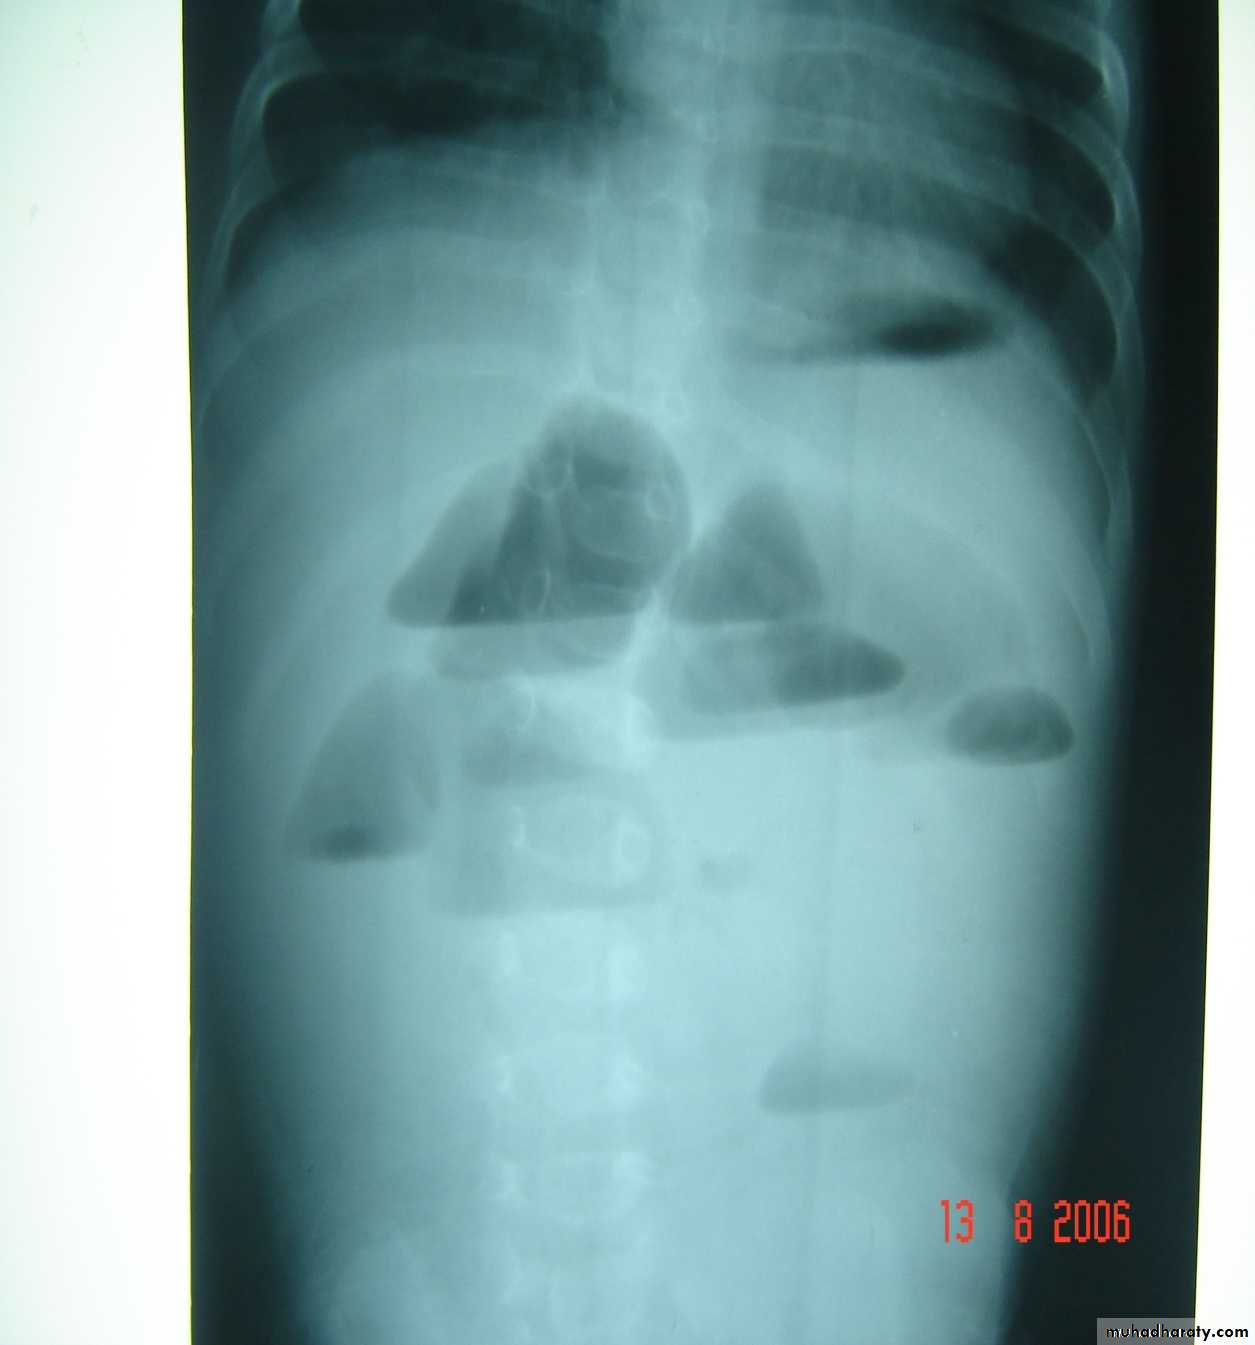

Intussusception

Pediatric surgery practical